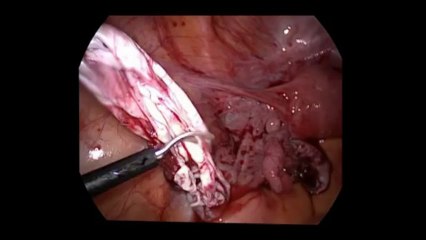

Laparoskopi ile Endometiroma (Çikolata kisti) operasyonu 1 - Prof. Dr. Aydan Biri

Laparoskopi ile Endometiroma (Çikolata kisti) operasyonu 1 - Prof. Dr.